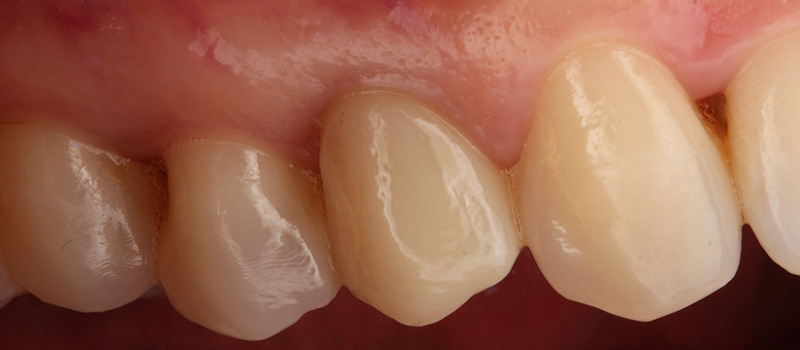

Fig. 05 : situation clinique à J10 (avant la dépose de la suture en 6.0 monofilament) vue latérale et vue vestibulaire.

7. La couronne d’usage